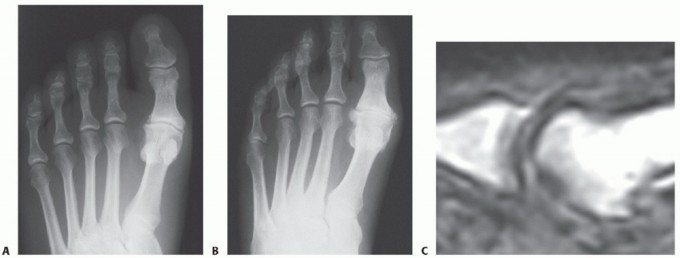

FIGURE 88-78 A: Normal anatomy of the first metatarsophalangeal joint, demonstrating the relationship of the metatarsal head to the proximal phalanx and the underlying sesamoid complex.

FIGURE 88-78 B: Type I dislocation. The intact intersesamoid ligament traps the metatarsal head, making closed reduction impossible.

FIGURE 88-78 C: Type IIA dislocation. The ruptured intersesamoid ligament typically allows for successful closed reduction.

FIGURE 88-78 D: Type IIB dislocation. The sesamoid fracture acts as a release, often permitting closed reduction, though surgical repair may be indicated for the fracture.

Standard weight-bearing (if possible) anteroposterior (AP), lateral, and oblique radiographs of the foot are mandatory. The lateral view is critical for assessing the dorsal displacement of the proximal phalanx and the position of the sesamoids relative to the metatarsal head. Computed Tomography (CT) may be utilized if an occult intra-articular fracture is suspected.

FIGURE 88-79 A: Preoperative radiograph demonstrating a severely displaced intra-articular phalangeal fracture associated with joint subluxation.

FIGURE 88-79 B: Postoperative radiograph showing anatomic reduction and stabilization of the phalangeal fracture using crossed Kirschner wires.